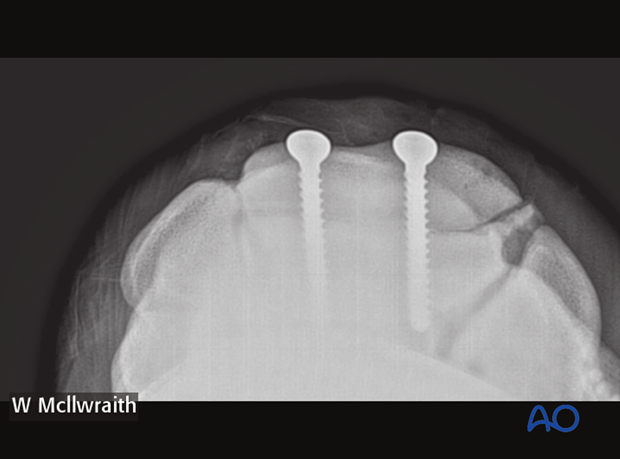

Reduction of the fracture is achieved by flexion of the carpal region. Sometimes prior removal of bone fragments and debris is necessary to achieve reduction. Frontal fractures of the both facets of the third carpal bone are repaired with two cortex screws of 4.5 mm diameter. Very occasionally three screws are deemed necessary.

Preparation of the thread hole, countersinking, determining the depth of the hole and tapping of the thread hole are subsequently performed, followed by inserting and tightening of the second screw. After the screws are tightened remove any debris or elevated cartilage at the fracture line.

Pearl: Use two fingers and thumb when doing final tightening, thereby avoiding excessive torque and potential breaking of screw head. Intraoperative radiographs are taken to confirm screw length and correct positioning.

Intraoperative radiographs are taken to confirm screw length and correct positioning.